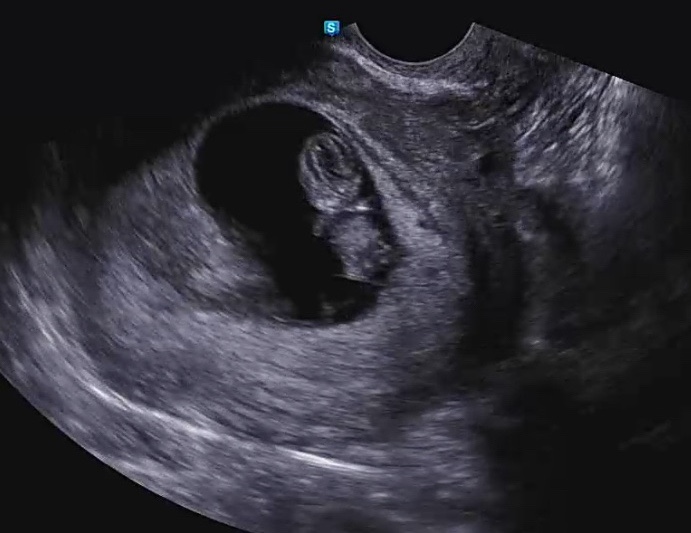

입덧시기 / 태아 성별 확인 / 성별 초음파 / 성별 반전 / 임신 11주 12주 15주 16주 20주 21주

안녕하세요 ☺️ 임테기로 임신확인하고 병원 다녀왔던 지난번 포스팅 후에 이번에는 성별확인 포스팅으로 ...

임신 초기 피비침 / 입덧 증상 / 초음파 젤리곰 보는 시기 / 임신 8주 9주 10주 / 태아 성별 확인 /성별 반전

저번 포스팅에서 임테기로 임신을 확인 후, 임신5주차에 아기집을 확인하고 6주차에 난황을 봤었어요 그리...